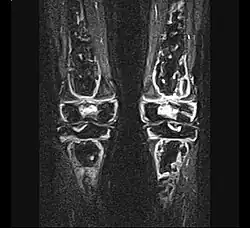

Klinik

Die Substanzdefekte des Knochens können bisweilen folgenlos bleiben oder zu schweren, unumkehrbaren Schäden an Gelenken und Knochen führen. Der Verlauf ist in Abhängigkeit von der Lokalisation, der Ausdehnung, den möglicherweise vorhandenen Risikofaktoren, dem Alter und dem letztendlichen Auslöser variabel. Sowohl Spontanheilungen wie auch völlige Gelenkzerstörungen sind bekannt. Prinzipiell können alle Knochen des Körpers betroffen sein. Es sind sowohl einseitige als auch beidseitige (symmetrische) Schädigungen bekannt. Knochennekrosen können in jedem Lebensalter auftreten.

- Stadium ARCO 0

Im Anfangsstadium sind in konventionellen Röntgenaufnahme keine krankhaften Veränderungen zu erkennen. In seltenen Fällen ist eine dezente Auflockerung der Knochenfeinstruktur (Trabekel) in dem betroffenen Areal zu erkennen: das Ausmaß dieser Auflockerung ist jedoch zumeist so gering, dass es nicht sicher erkannt werden kann. In der Kernspintomographie (MRT) ist in diesem Stadium ein Bild analog dem Knochenmarködem (KMÖ, transiente Osteoporose; bone marrow edema, BME) zu erkennen. Unter Verwendung der short tau inversion recovery (STIR) Aufnahmesequenz wird eine Signalhyperintensität (helles Aufleuchten im Graustufen-Kernspinbild) festgestellt (vergleiche Bild 1a und 2 helle Ränder). Eine sichere Unterscheidung zwischen dem prinzipiell reversiblen Bild eines KMÖ/BME und dem Stadium ARCO I einer aseptischen Knochennekrose ist nicht mittels des Kernspintomogramms möglich.